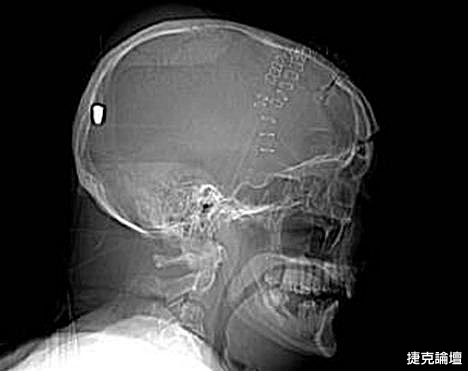

據英國《每日郵報》5月11日報導,英國一名61歲的老人上個月19日在花園工作時被一顆流彈擊中腦部竟奇跡存活,目前他半身癱瘓但無生命危險。5月10日,警方為了破案公佈了彼得先生的腦部掃描圖片,希望知情者提供相關線索。

事情的經過是這樣的,彼得在整理花園的時候突然摔倒在地不省人事,他的家人還以為他中風了,但醫院對其大腦掃描後卻發現了令人驚悚的事實:一顆子彈不知由於何種原因從左眼窩進入他的大腦,並深深植入其腦後部。但不可思議的是彼得竟然活了下來,雖然身體部分癱瘓且失去了語言和記憶能力。

醫生說開顱取彈手術風險巨大,很可能危及彼得生命,所以只能放棄這個計劃。彼得先生已經被告知事故經過,但他自己什麼也想不起來了,醫生認為他患了健忘症。除了損傷左眼視力外,彼得先生身體右下半部分也已癱瘓。他的發音都很含糊,記憶也是支離破碎的,目前大部分時間都在睡覺,但病情還算穩定。

負責調查此案的警官史蒂夫表示:“這可能是我調查過的最詭異的一個案子了。”經過對掃描圖片的鑒定,警方彈道專家賈爾斯認為這顆子彈很像是從一種通常用於射殺兔子的.22口徑獵槍裡射出的。

“如果在10碼外開這種槍,子彈會穿透彼得的腦部,但若是從800到1000碼以外,子彈會失去大部分的衝擊力,只能穿透軟組織。所以說,在這個距離內,子彈若射中彼得腦殼會被彈回,不可能進入腦中,”賈爾斯說。